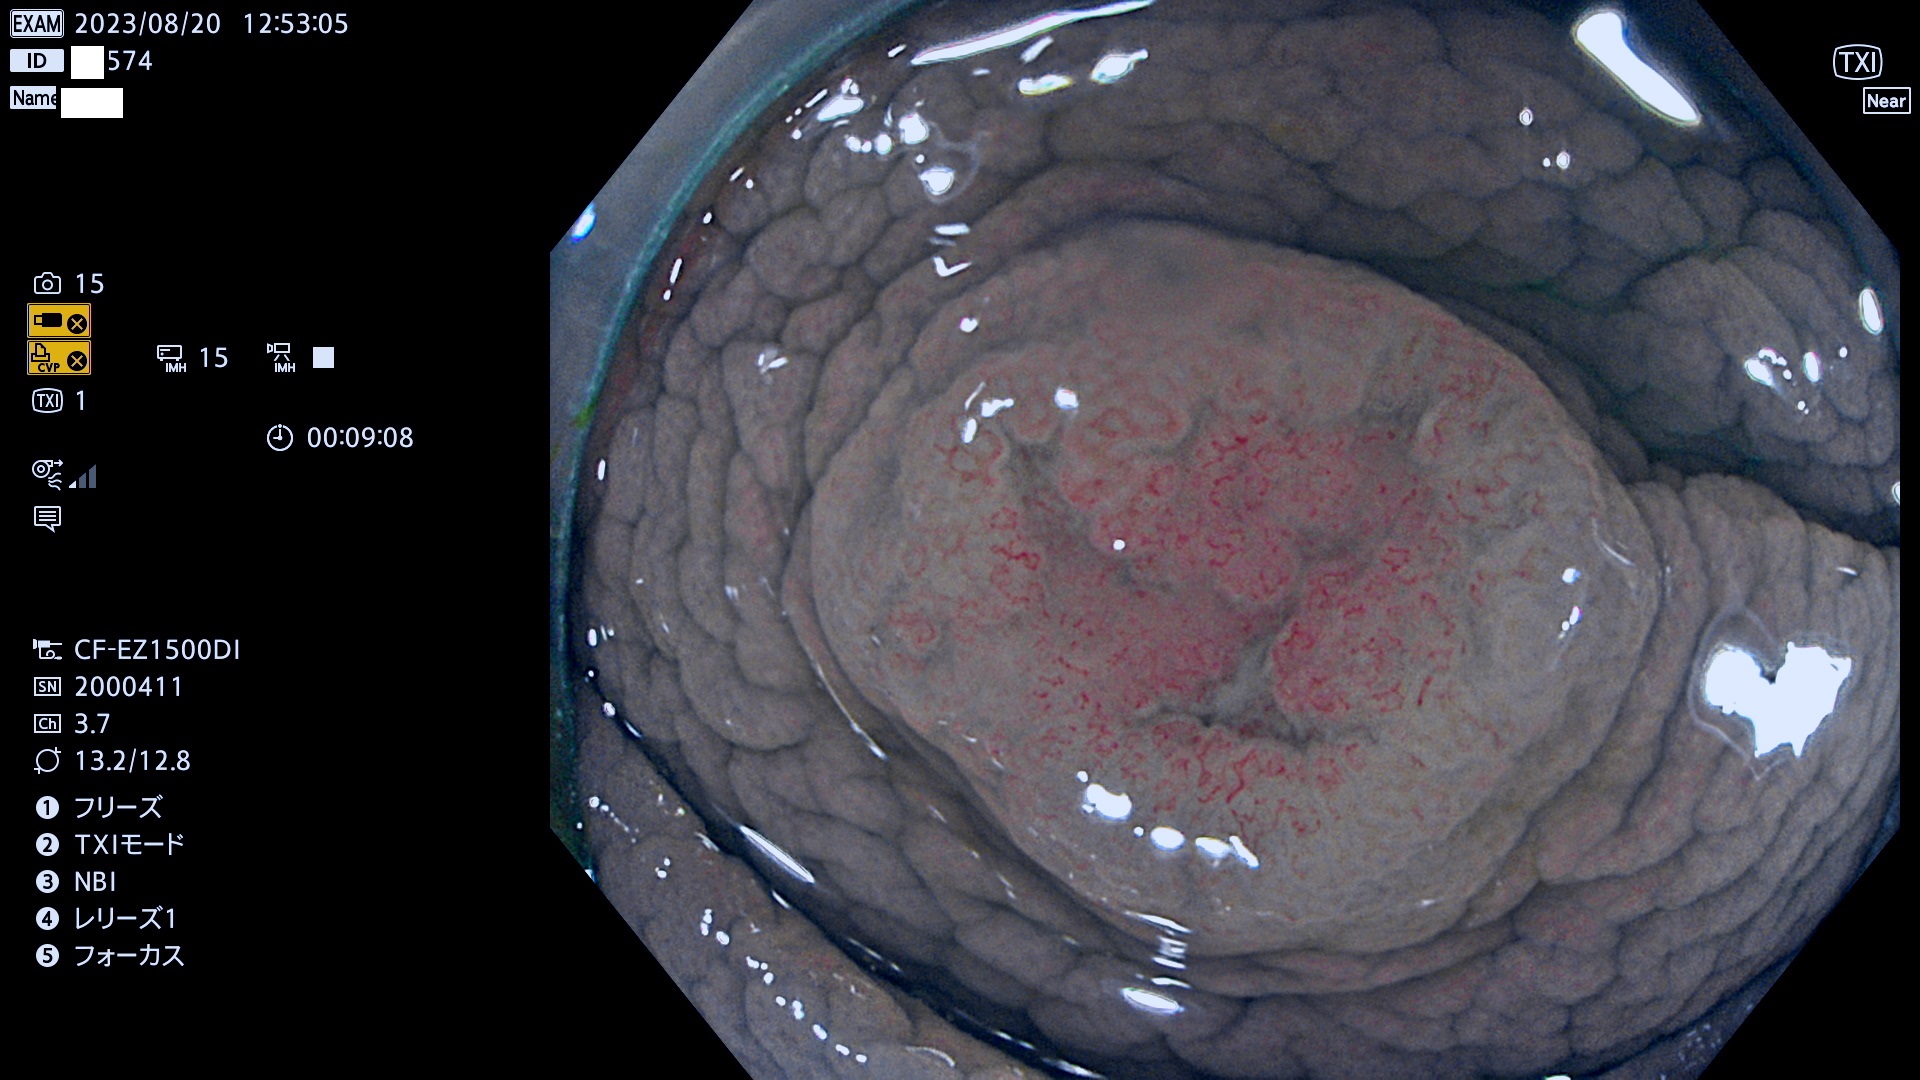

表面型腺腫(Flat Adenoma)の中で、完全に平坦な物をUb、陥凹している物をUcと呼びます。平坦隆起型(Ua)よりも、発見が難しく危険な病変です。このタイプは「内視鏡後・大腸癌の重要犯人」であり、この発見率は「腺腫発見率」よりも、重要な意味があります。

専門的)何故、陥凹していると危険? 癌遺伝子の変異が蓄積すると細胞分裂が盛んになり隆起するのでは?と通常は思われるでしょう。しかし実際は逆です。これは2022年の記事にある「細胞はストレスに直面したら細胞分裂を止める(細胞老化に入り休眠する)という生命の基本的現象」によるものです(Oncogene Stress)。細胞老化を起こすのが癌抑制遺伝子で、この安全装置(ブレーキ)が壊れると癌になります(休眠からの覚醒)。ですから陥凹は「まだ癌では無いが癌化の直前」を意味します。特に「小サイズなのに陥凹している」病変は短期間に腫瘍進化(⇒2021年記事)が起きたことを意味します(=ゲノム不安定性

専門的)Uc=De Novo癌? 内視鏡の解像度が低かった時代、このような説もありました。しかし今日の高精度内視鏡では良性の微小なUc型腺腫が日常的に見つかります。私見ですが「Ucこそが多段階発癌(Adenoma-Carcinoma Sequence)のMain Route」と考えます。

毎週の検査(木・金・土・日)に発見されたUb、Uc型・腺腫を、その週の日曜の夜にUPし1週間、提示します。

抽出の対象期間 2023年8月17日(木)〜8月20(日)の4日間(48件の検査)11件